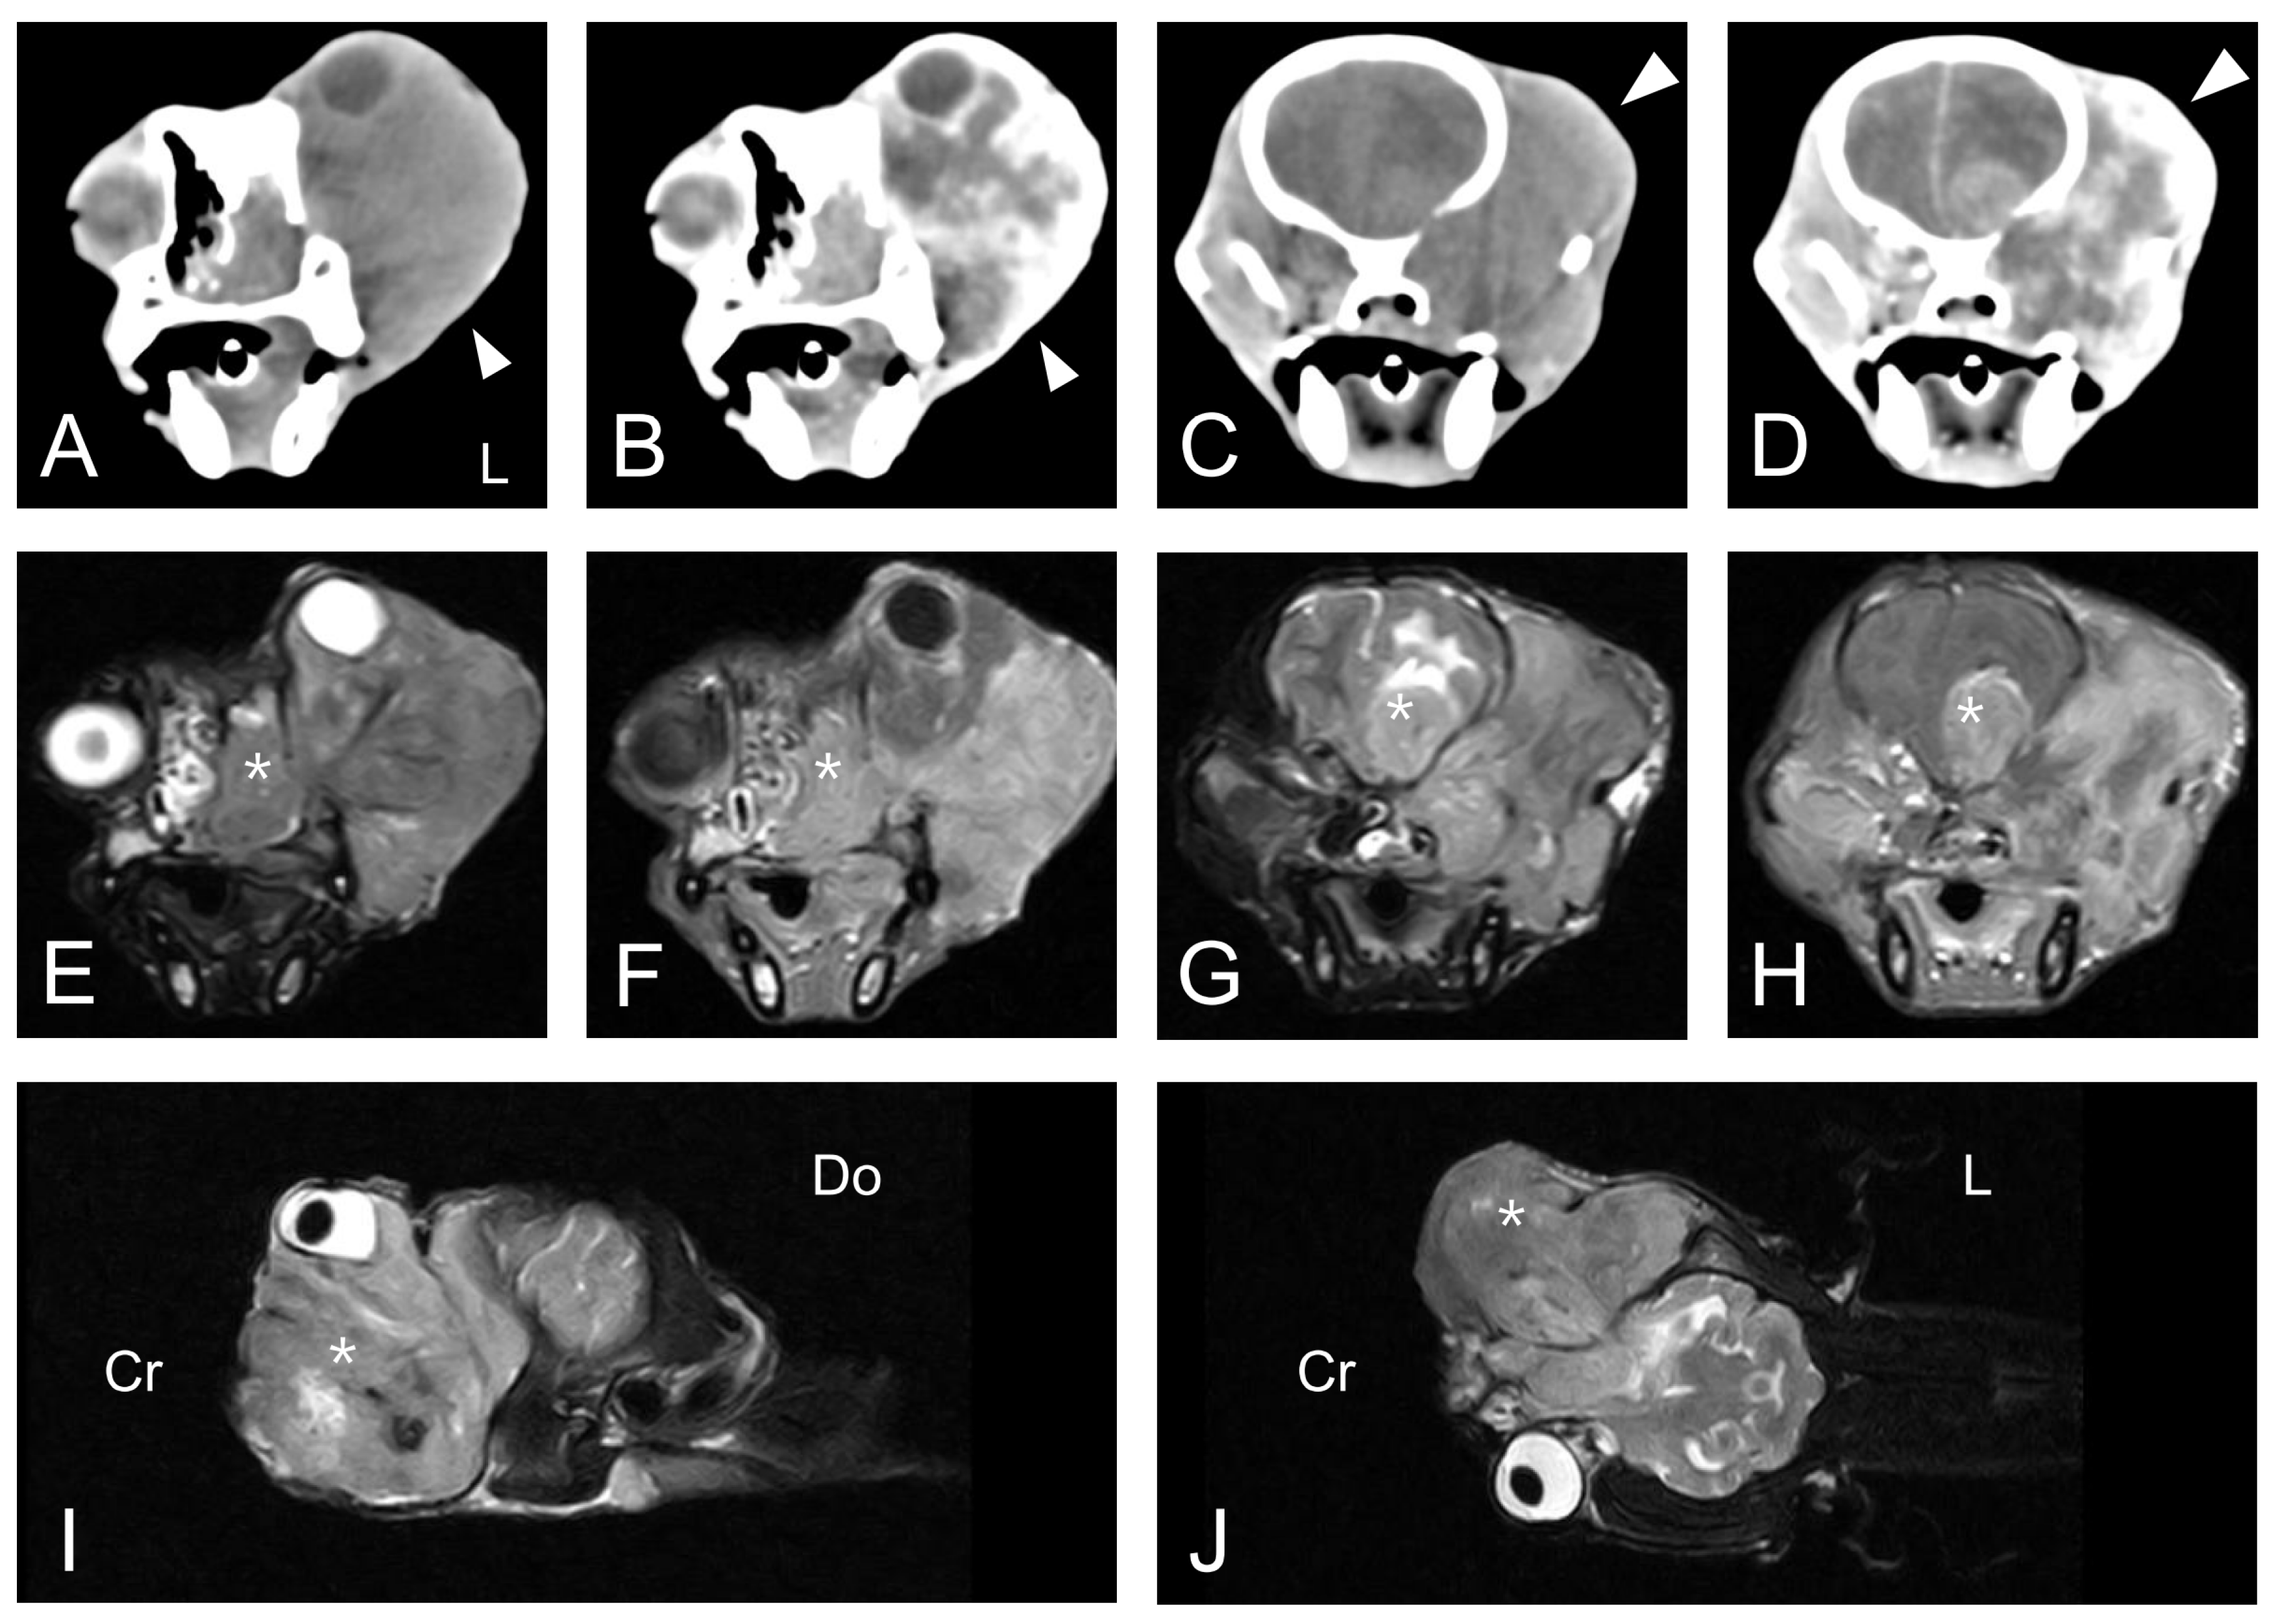

The dog underwent computed tomography (CT) and magnetic resonance imaging (MRI). CT was performed using the Somatom Emotion Duo scan system (Siemens Medical Systems, Munich, Germany). Pre-contrast and post-contrast transverse images with a 3-mm slice thickness were obtained. All post-contrast images were obtained following the injection of intravenous iohexol (Omnipaque 300; GE-Healthcare, Little Chalfont, United Kingdom) at a dose of 0.9 g I/kg body weight. MRI was performed using the APERTO 0.4 T scanner (Hitachi Medical Corporation, Tokyo, Japan). T1-weighted (T1W) images, T2-weighted (T2W) images, fluid-attenuated inversion recovery (FLAIR) images, and contrast-enhanced T1-weighted (CET1W) images were obtained from the MRI scan. CET1W images were obtained after intravenous injection of gadolinium EDTA (Omniscan; GE-Healthcare, Little Chalfont, United Kingdom) at a dose of 0.20 mmol/kg body weight. CT scan of the head revealed an ill-defined, heterogeneous, isoattenuating to hyperattenuating, contrast-enhanced soft tissue mass in the left orbit with superior displacement of the left globe (Figure 2A–D). The mass completely occupied the posterior aspect of the lateral nasal cavity and the left pterygopalatine fossa. It also exhibited invasion of the skull base with lysis of the adjacent bone, including the maxilla, cribriform plate, and basisphenoid. Whole-body CT scan could not find any evidence of an extraocular primary tumor or distant metastases. An MRI scan at the same anatomic level as the CT scan revealed an equivalent mass in the left retrobulbar space extending into the nasal cavity and into the frontal lobes of the brain with destruction of the adjacent cribriform plate and the basisphenoid bone (Figure 2E–J). The lesion was hyperintense on T2W and FLAIR images, hypointense on T1W images, and irregularly enhanced on CET1W images. The space-occupying mass with vasogenic edema caused a significant mass effect and midline shift to the affected side of the brain.

Figure 2.

Transverse-plane computed tomography (CT) images (A–D), magnetic resonance images (MRI) (E–H) at the level of the eye globes and the brain, and left parasagittal (I) and dorsal plane (J) MRI are depicted. Both pre-contrast (A,C) and post-contrast (B,D) CT images demonstrated an ill-defined, heterogeneous, contrast-enhanced soft tissue mass (arrowhead) extending from the left nasal cavity to the left pterygopalatine fossa. Sequential MRI revealed an equivalent lesion that was hyperintense on T2W (E,G,I,J) and irregularly enhanced on CET1W images (F,H). The space-occupying mass (asterisk) with vasogenic edema caused significant mass effect and midline shift to the affected side of the brain. L, left; Cr, cranial; Do, dorsal.